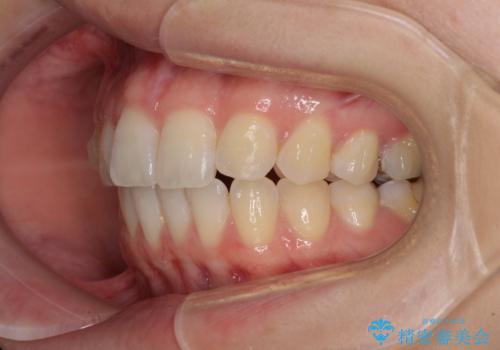

気になる上の歯を改善 インビザライン矯正

- 矯正治療の後戻りが気になるとのことで来院された患者様です。

上顎の後戻りをインビザライン・ライトで治療することとしました。

上顎のみの治療を希望されたため、咬み合わせをしっかりと改善することはできませんでしたが、審美面が大きく改善され、日常生活の機能面でも不具合を感じることはなく、大変満足していただきました。